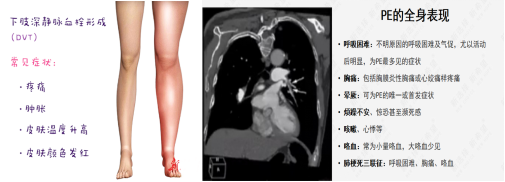

以肺血栓栓塞癥(PTE)為主要臨床類型的肺栓塞(PE)和深靜脈血栓形成(DVT)合稱為靜脈血栓栓塞癥(VTE),是同一疾病在不同階段、不同部位的兩種重要臨床表現(xiàn)形式。臨床上諸多科室的患者均存在VTE風(fēng)險(xiǎn),其發(fā)病隱匿、臨床癥狀不典型,容易誤診、漏診,一旦發(fā)生,致死和致殘率高; DissolVE-2 研究表明[1],我國(guó)的外科住院患者 VTE 中、 高風(fēng)險(xiǎn)比例高達(dá)86.1%,內(nèi)科患者 VTE 高風(fēng)險(xiǎn)比例為 36.6%;文獻(xiàn)報(bào)道美國(guó)每年死于VTE患者25萬(wàn)至30萬(wàn)。除了死亡之外,未能及時(shí)處理的VTE,多數(shù)不能幸免于深靜脈血栓后遺癥(PTS)的發(fā)生,造成患者長(zhǎng)期病痛,影響生活和工作能力,嚴(yán)重者可致殘。

肺栓塞(PE)的觀察及護(hù)理:

下肢DVT最嚴(yán)重的并發(fā)癥是肺栓塞。肺栓塞急性期病人應(yīng)絕對(duì)臥床休息10~14天,床上活動(dòng)時(shí)避免動(dòng)作幅度過(guò)大,禁止按摩、擠壓或熱敷患肢,保持大便通暢,避免屏氣用力的動(dòng)作,以防血栓脫落。若病人出現(xiàn)胸痛、呼吸困難、血壓下降等異常情況,提示可能發(fā)生肺栓塞,應(yīng)立即囑病人平臥,避免做深呼吸、咳嗽、劇烈翻動(dòng),同時(shí)給予高濃度氧氣吸入,并報(bào)告醫(yī)師,配合搶救。